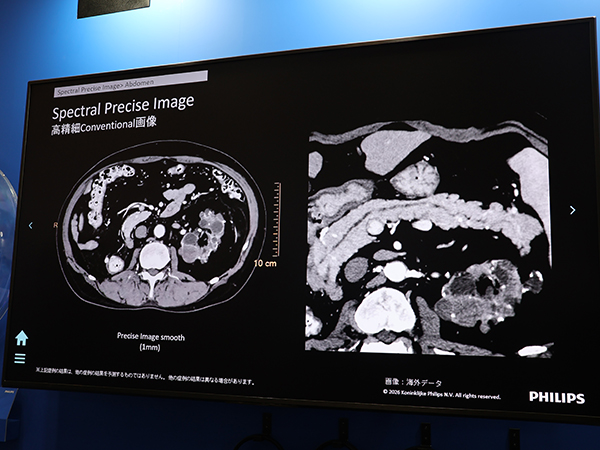

新製品の「Verida」は,2層検出器によるマルチエナジースペクトラルCTとして世界で初めてイメージングチェーンにAIを統合した装置である。搭載される検出器はAI画像再構成に最適化した第三世代へと進化。画像再構成の工程では,Multi-pass AIアルゴリズムを用いたAI画像再構成「Spectral Precise Image」によりコントラスト向上とノイズ低減を実現している。展示では,膵臓がんの早期発見や心不全パンデミックにフォーカスして製品の特長を紹介。心臓CTでは,Spectral Precise Image とAI技術を応用した「Precise Cardiac」を併用することで,高心拍例でもブレのない画像を得られることをアピールした。

膵臓がんの早期発見を支援するAI画像再構成「Spectral Precise Image」